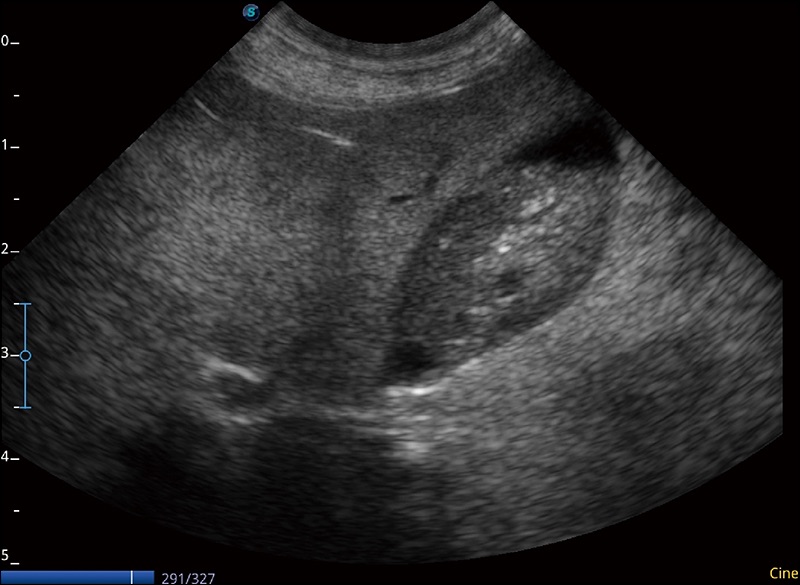

穿刺针增强

高清显示穿刺进针情况

连续波多普勒成像CW

为心脏功能评估提供更多诊断信息